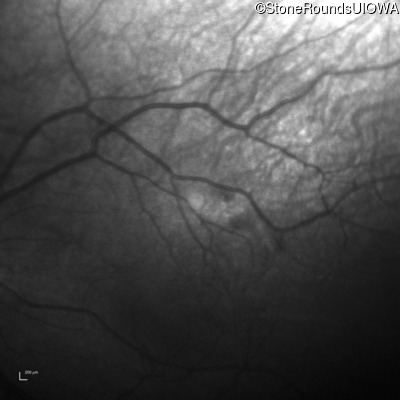

Visit at age: 4 months

Fundus Photography - Right - UCUSUM

Exemplar